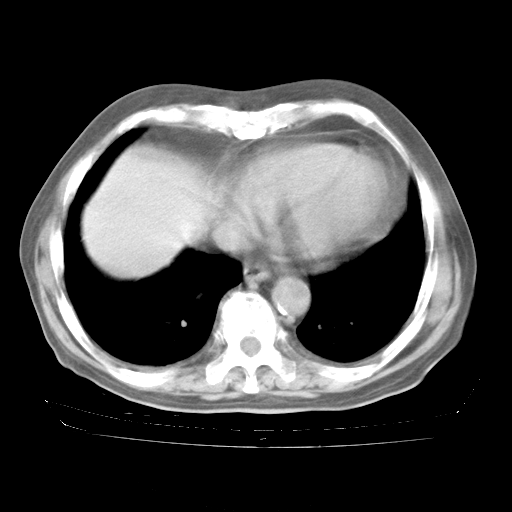

4月28日肺部CT